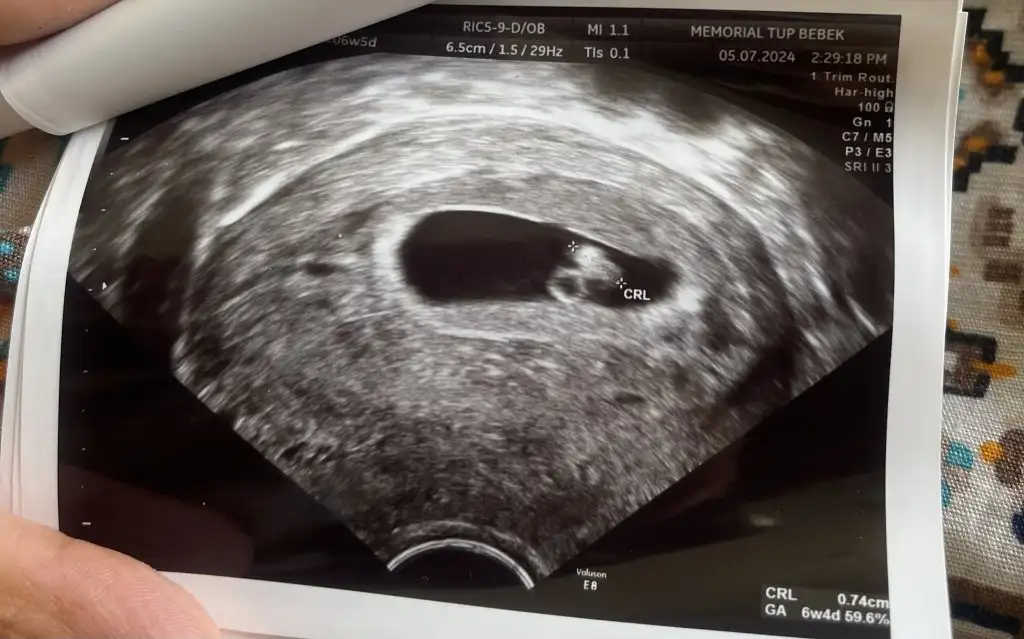

Benim ki de 7 haftalık sizce nedir cinsiyetiİçime erkek doğdu.

Merhaba benim için de bakarmısınızNet erkek :) sağlıkla doğsun.